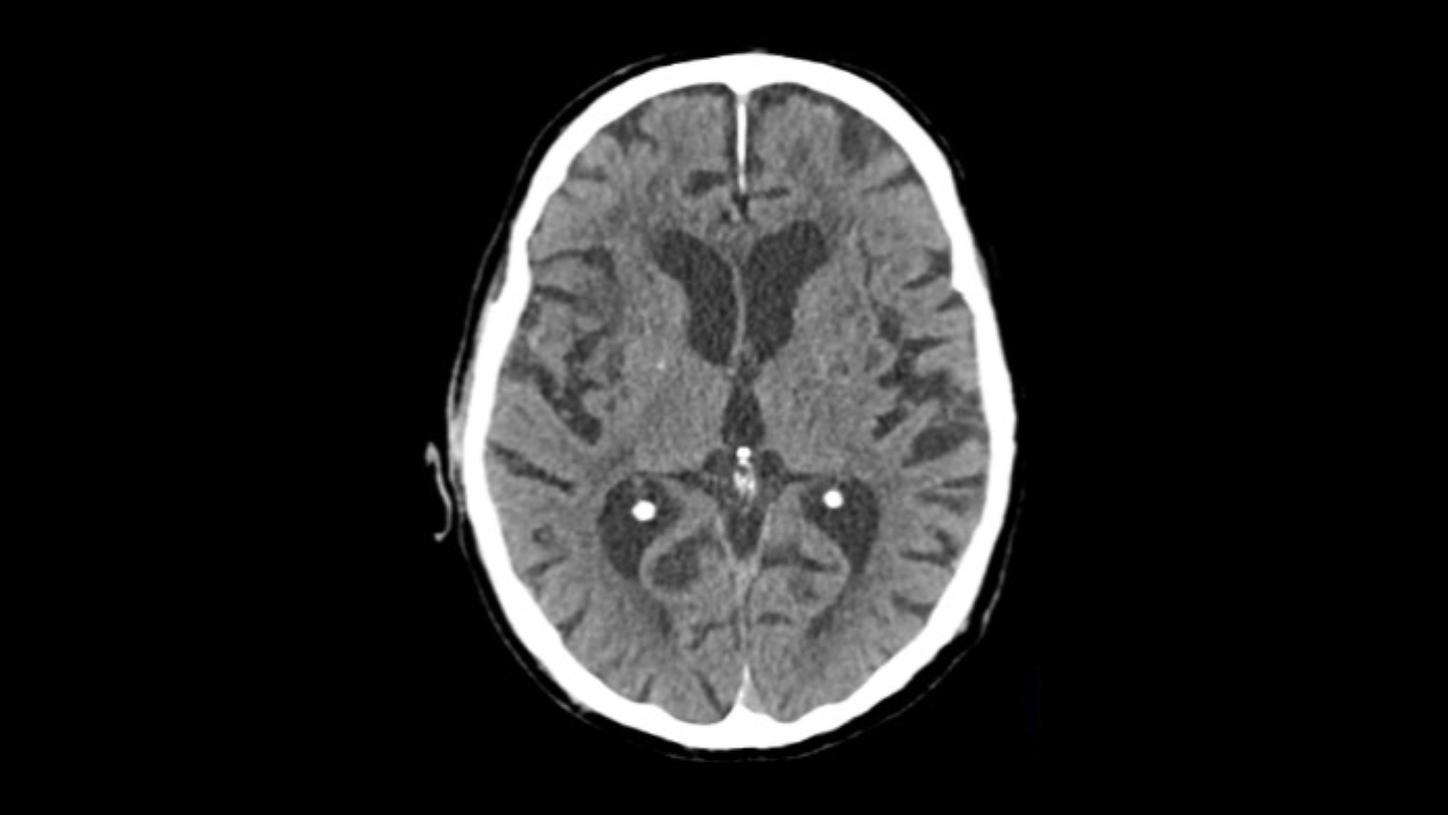

Native head scan

Assist with or support differential diagnosis of acute stroke with excellent gray-white matter differentiation and contrast enhancement

Native head scan

Assist with or support differential diagnosis of acute stroke with excellent gray-white matter differentiation and contrast enhancement